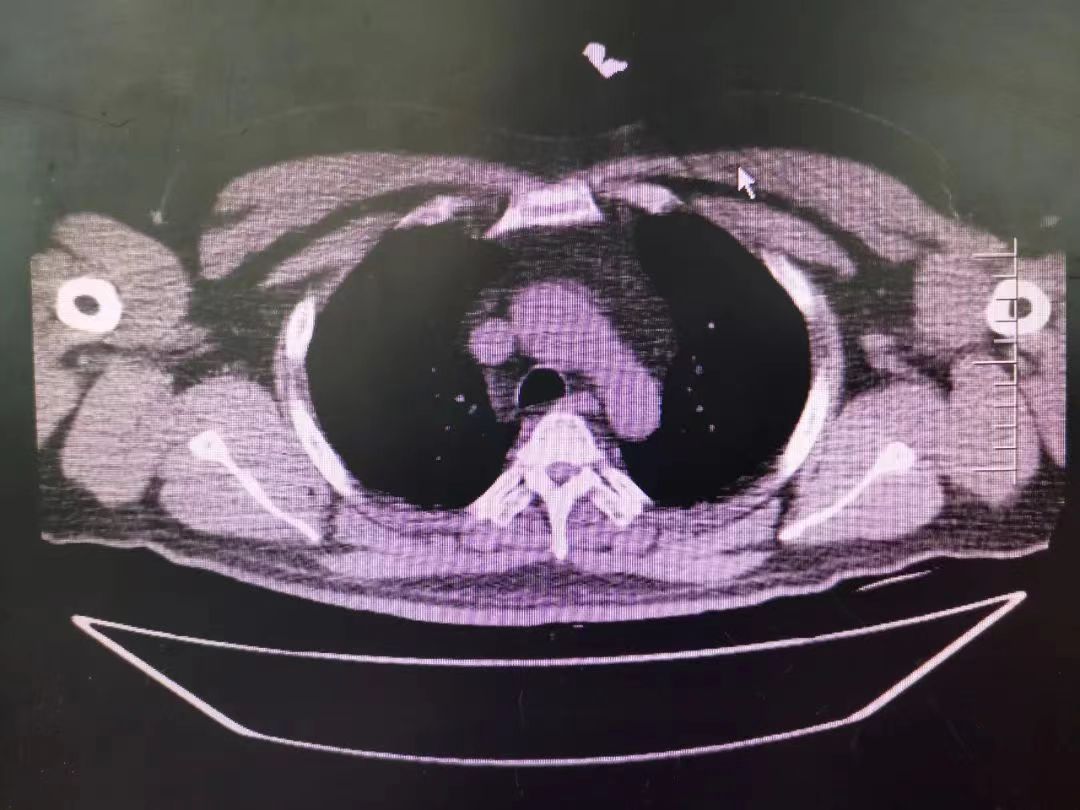

CT室門口,焦燥的家屬不停的走動著、等待著,看到醫生的到來,快速跑到醫生面前說:“醫生,快幫我看看,病人怎么樣”。陳醫生過去一看,一個體型偏胖的患者平躺在床上,一把剪刀齊根直插胸口觸目驚心,陳醫生不由眉頭一緊,轉身去看電腦CT影像 --剪刀斜著刺入胸骨,將胸骨完全穿透,刀尖距離心包約1-2mm,正下方是主動脈,大量心包積液?再一看,患者肥胖,脂肪組織多,不排除脂肪偽影。考慮患者血壓相對平穩,由于緊張導致心率快,立刻安撫患者,讓其保持安靜,盡量避免咳嗽,避免深呼吸和過多運動。隨即撥通了武小剛主任的電話:“主任,這有一位患者,銳器刺傷不排除已經損傷到心臟,病人目前血壓平穩”“嚴密監測患者病情變化,準備急診手術,我馬上到”武主任說。